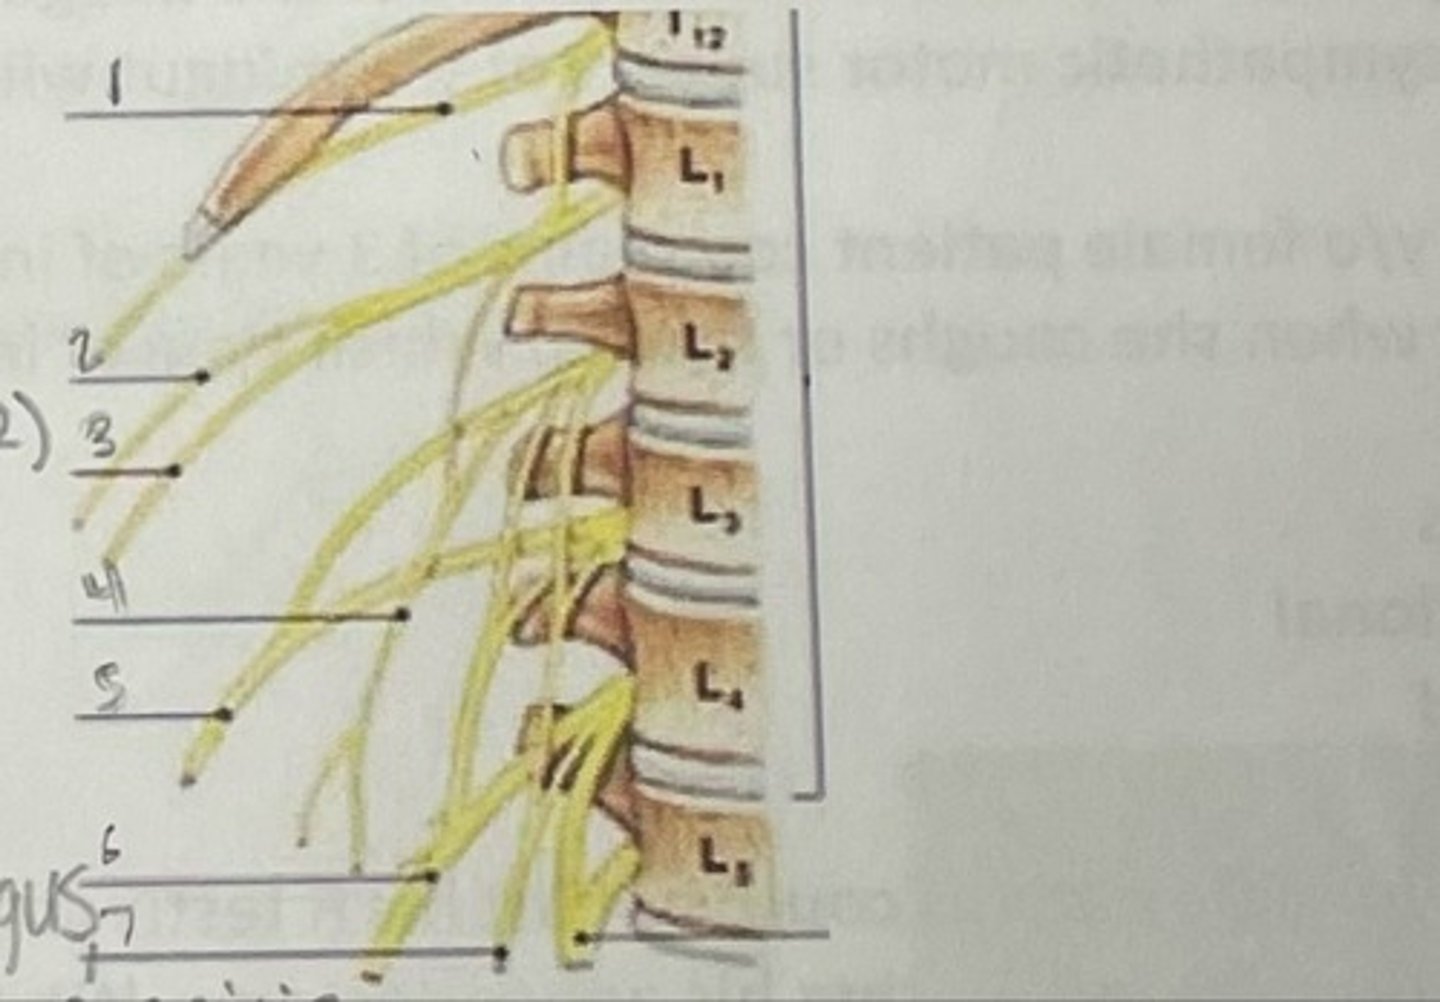

Subcostal nerve (T12)

What is 1

Illiohypogastric nerve (T12/L1)

What is 2

Illioinguinal nerve (L1)

What is 3

Genitofemoral nerve (L1-L2) ; on top of psoas

What is 4

lateral femoral cutaneous nerve (L2-L3)

What is 5

Femoral Nerve (L2-L4)

What is 6

Obturator nerve (L2-L4)

What is 7